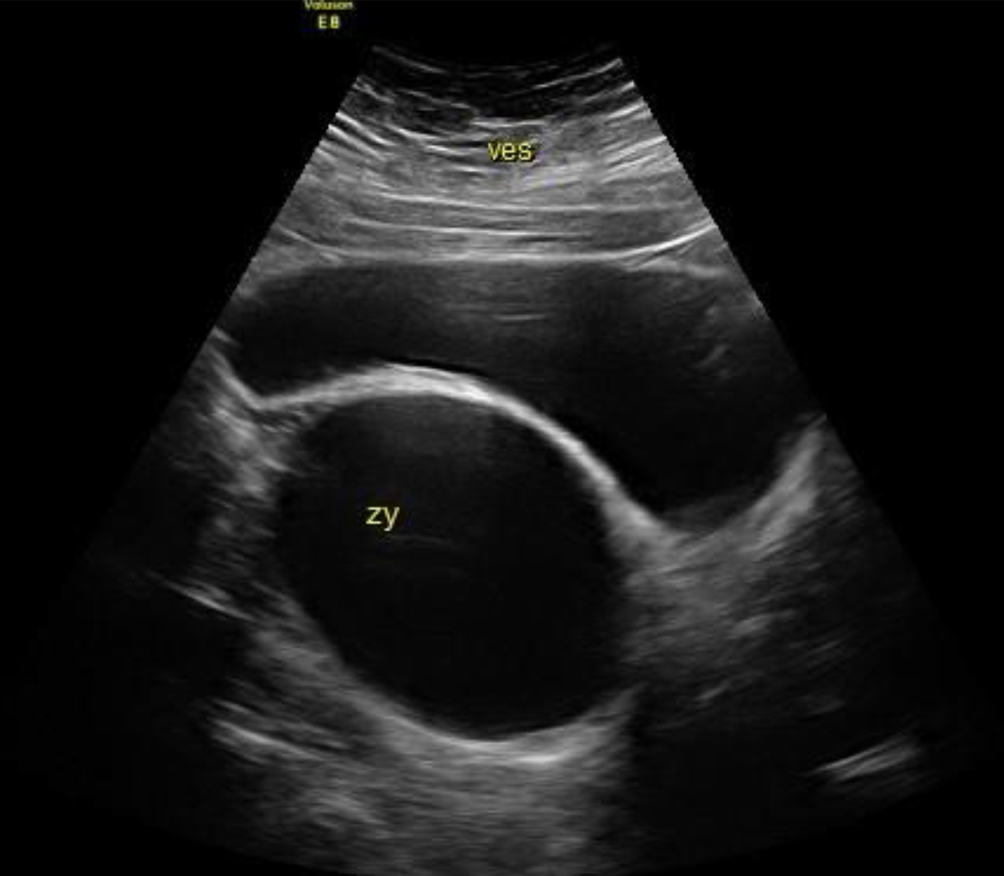

Abb. 1

Über Jahre konstante Gartner-Gang-Zyste mit 6 cm Längsdurchmesser (links, proximal der Blase), die trotz der unmittelbaren Nähe zur Blase der Patientin nie Beschwerden machte. Darüber die mäßig gefüllte Blase und der Uterus